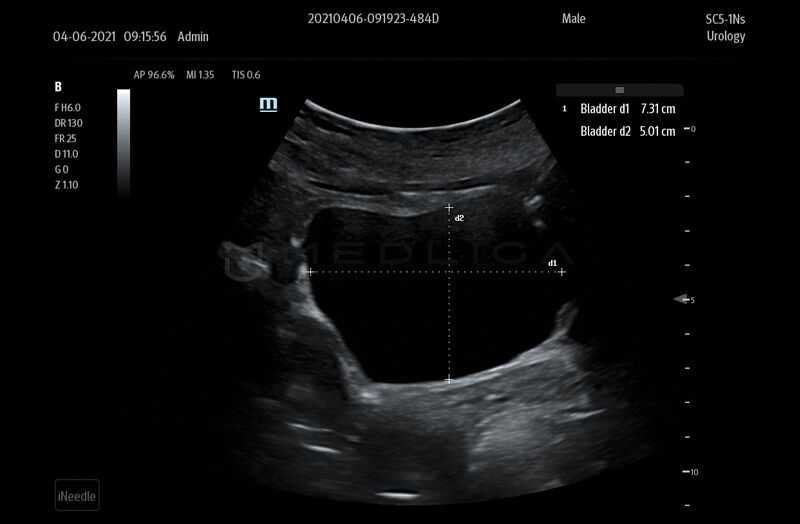

Smart Bladder